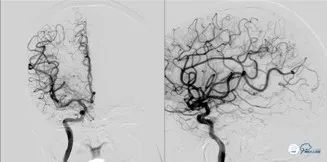

图3

图4

图5

可见基底动脉尖端部血栓,呈次全闭塞状态,前向血流Mtici 2*级A**,无明显前循环向后循环代偿。